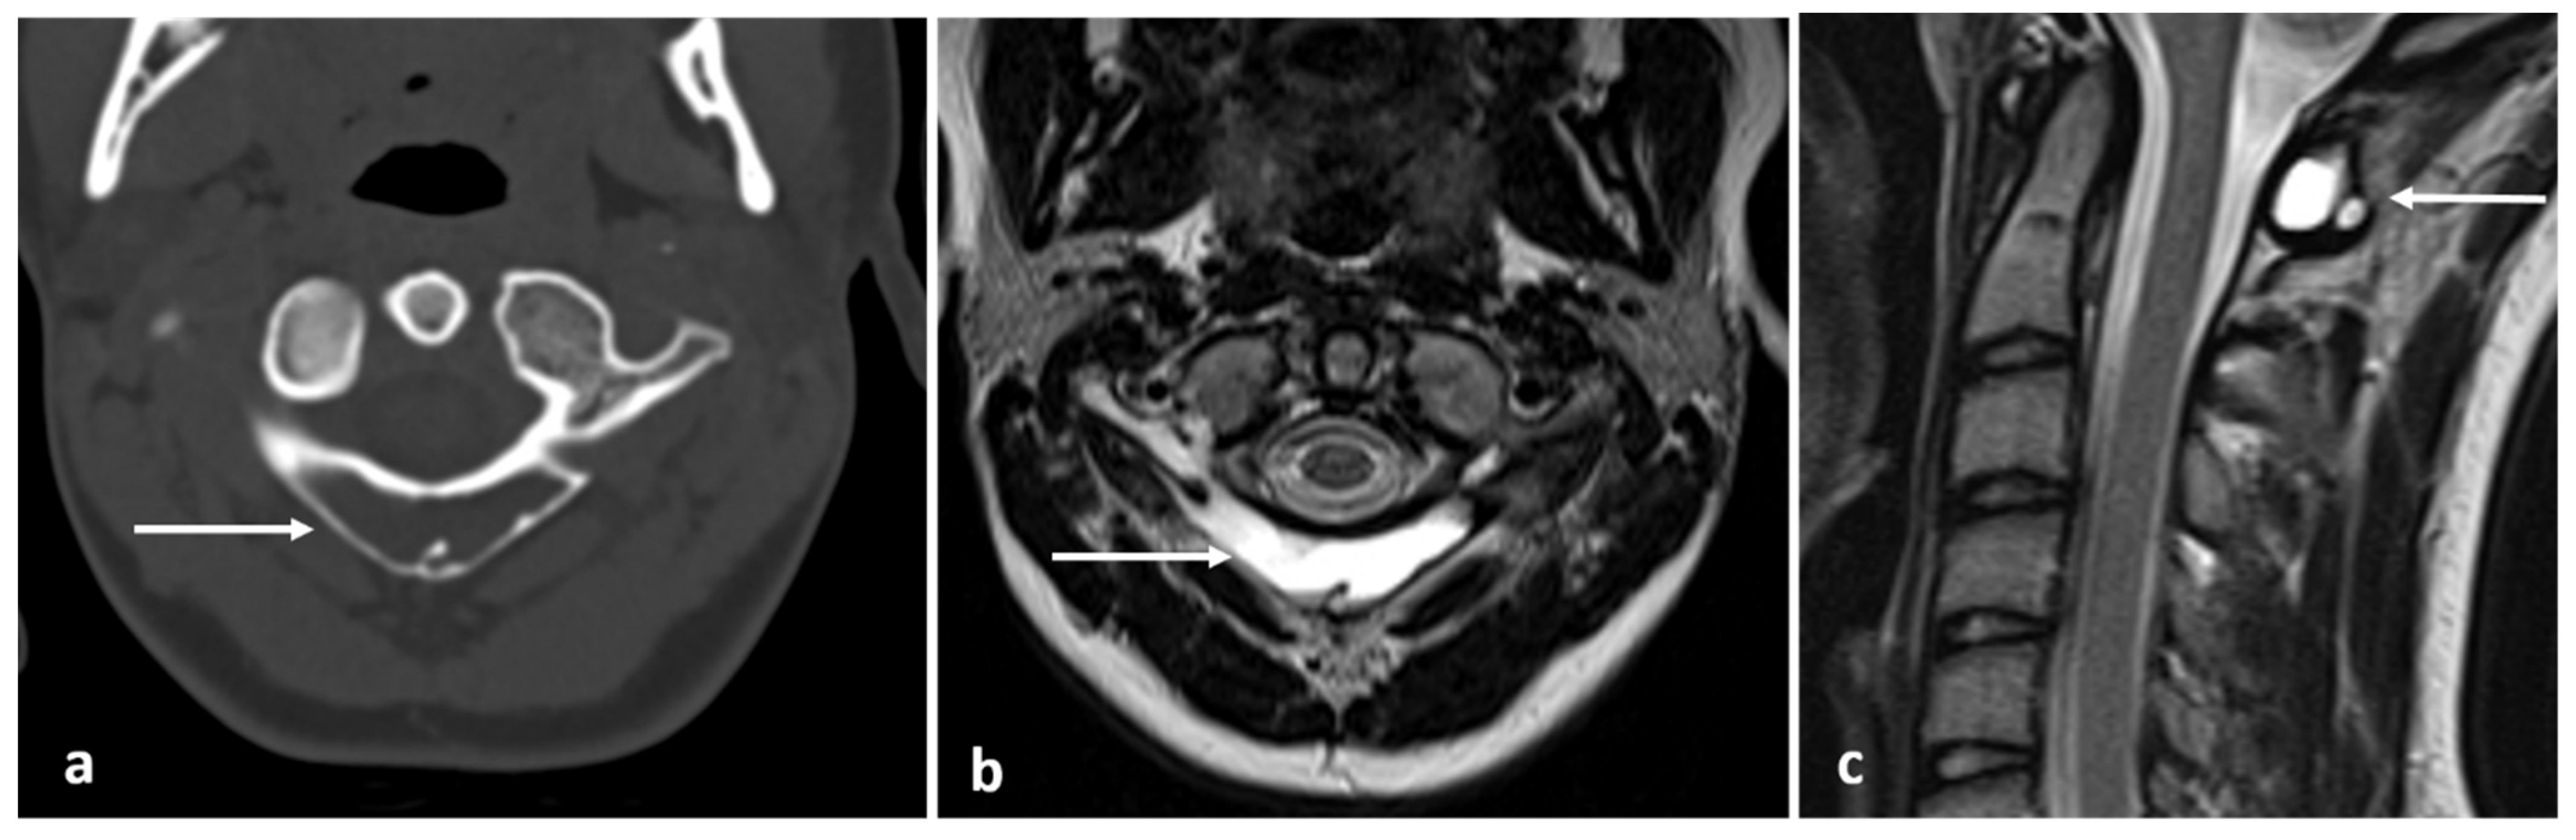

| Simple bone cyst | Well defined lucent rim with narrow zone of transition. | Fluid signal lesion. May have some internal haemorrhage (high T1 signal). |

| Eosinophilic granuloma | Lucent lytic lesion, with bone destruction. Vertebra plana. | Non-specific appearance, with low T1 and high T2 signal. Diffuse enhancement. |